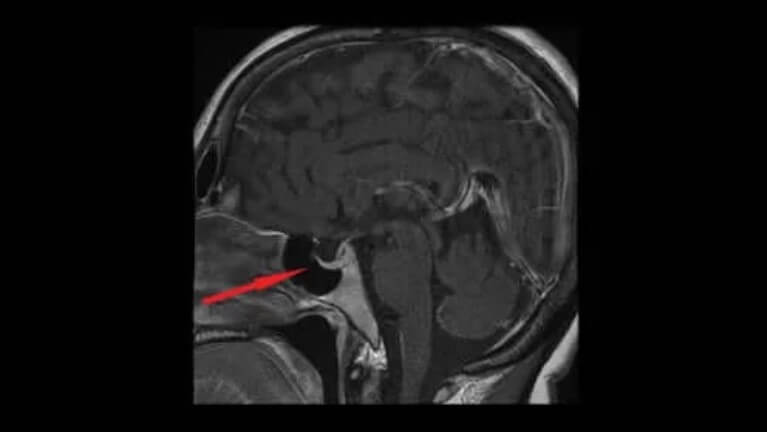

Η αγγειοπιεσίνη, επίσης γνωστή ως αντιδιουρητική ορμόνη ή ADH, βγαίνει από τους μαγνητοκυτταρικούς πυρήνες του υποθάλαμου. Από εκεί περνά στη νευροϋπόλυση και τέλος στο αίμα. Βοηθά στη ρύθμιση της ποσότητας νερού στο σώμα ελέγχοντας την ποσότητα νερού που εκκρίνουν τα νεφρά. Σε αυτό το άρθρο θα εξετάσουμε τα διαφορετικά χαρακτηριστικά και τις επιδράσεις της αγγειοπιεσίνης.

Τα χαμηλά επίπεδα της αντιδιουρητικής ορμόνης θα κάνουν τα νεφρά να εκκρίνουν περίσσεια νερού. Ο όγκος των ούρων θα αυξηθεί και θα οδηγήσει σε αφυδάτωση και μείωση της αρτηριακής πίεσης. Έτσι, τα χαμηλά επίπεδα αντιδιουρητικής ορμόνης μπορεί να υποδηλώνουν βλάβη στον υποθάλαμο ή την υπόφυση ή την πρωτογενή πολυδιψία.